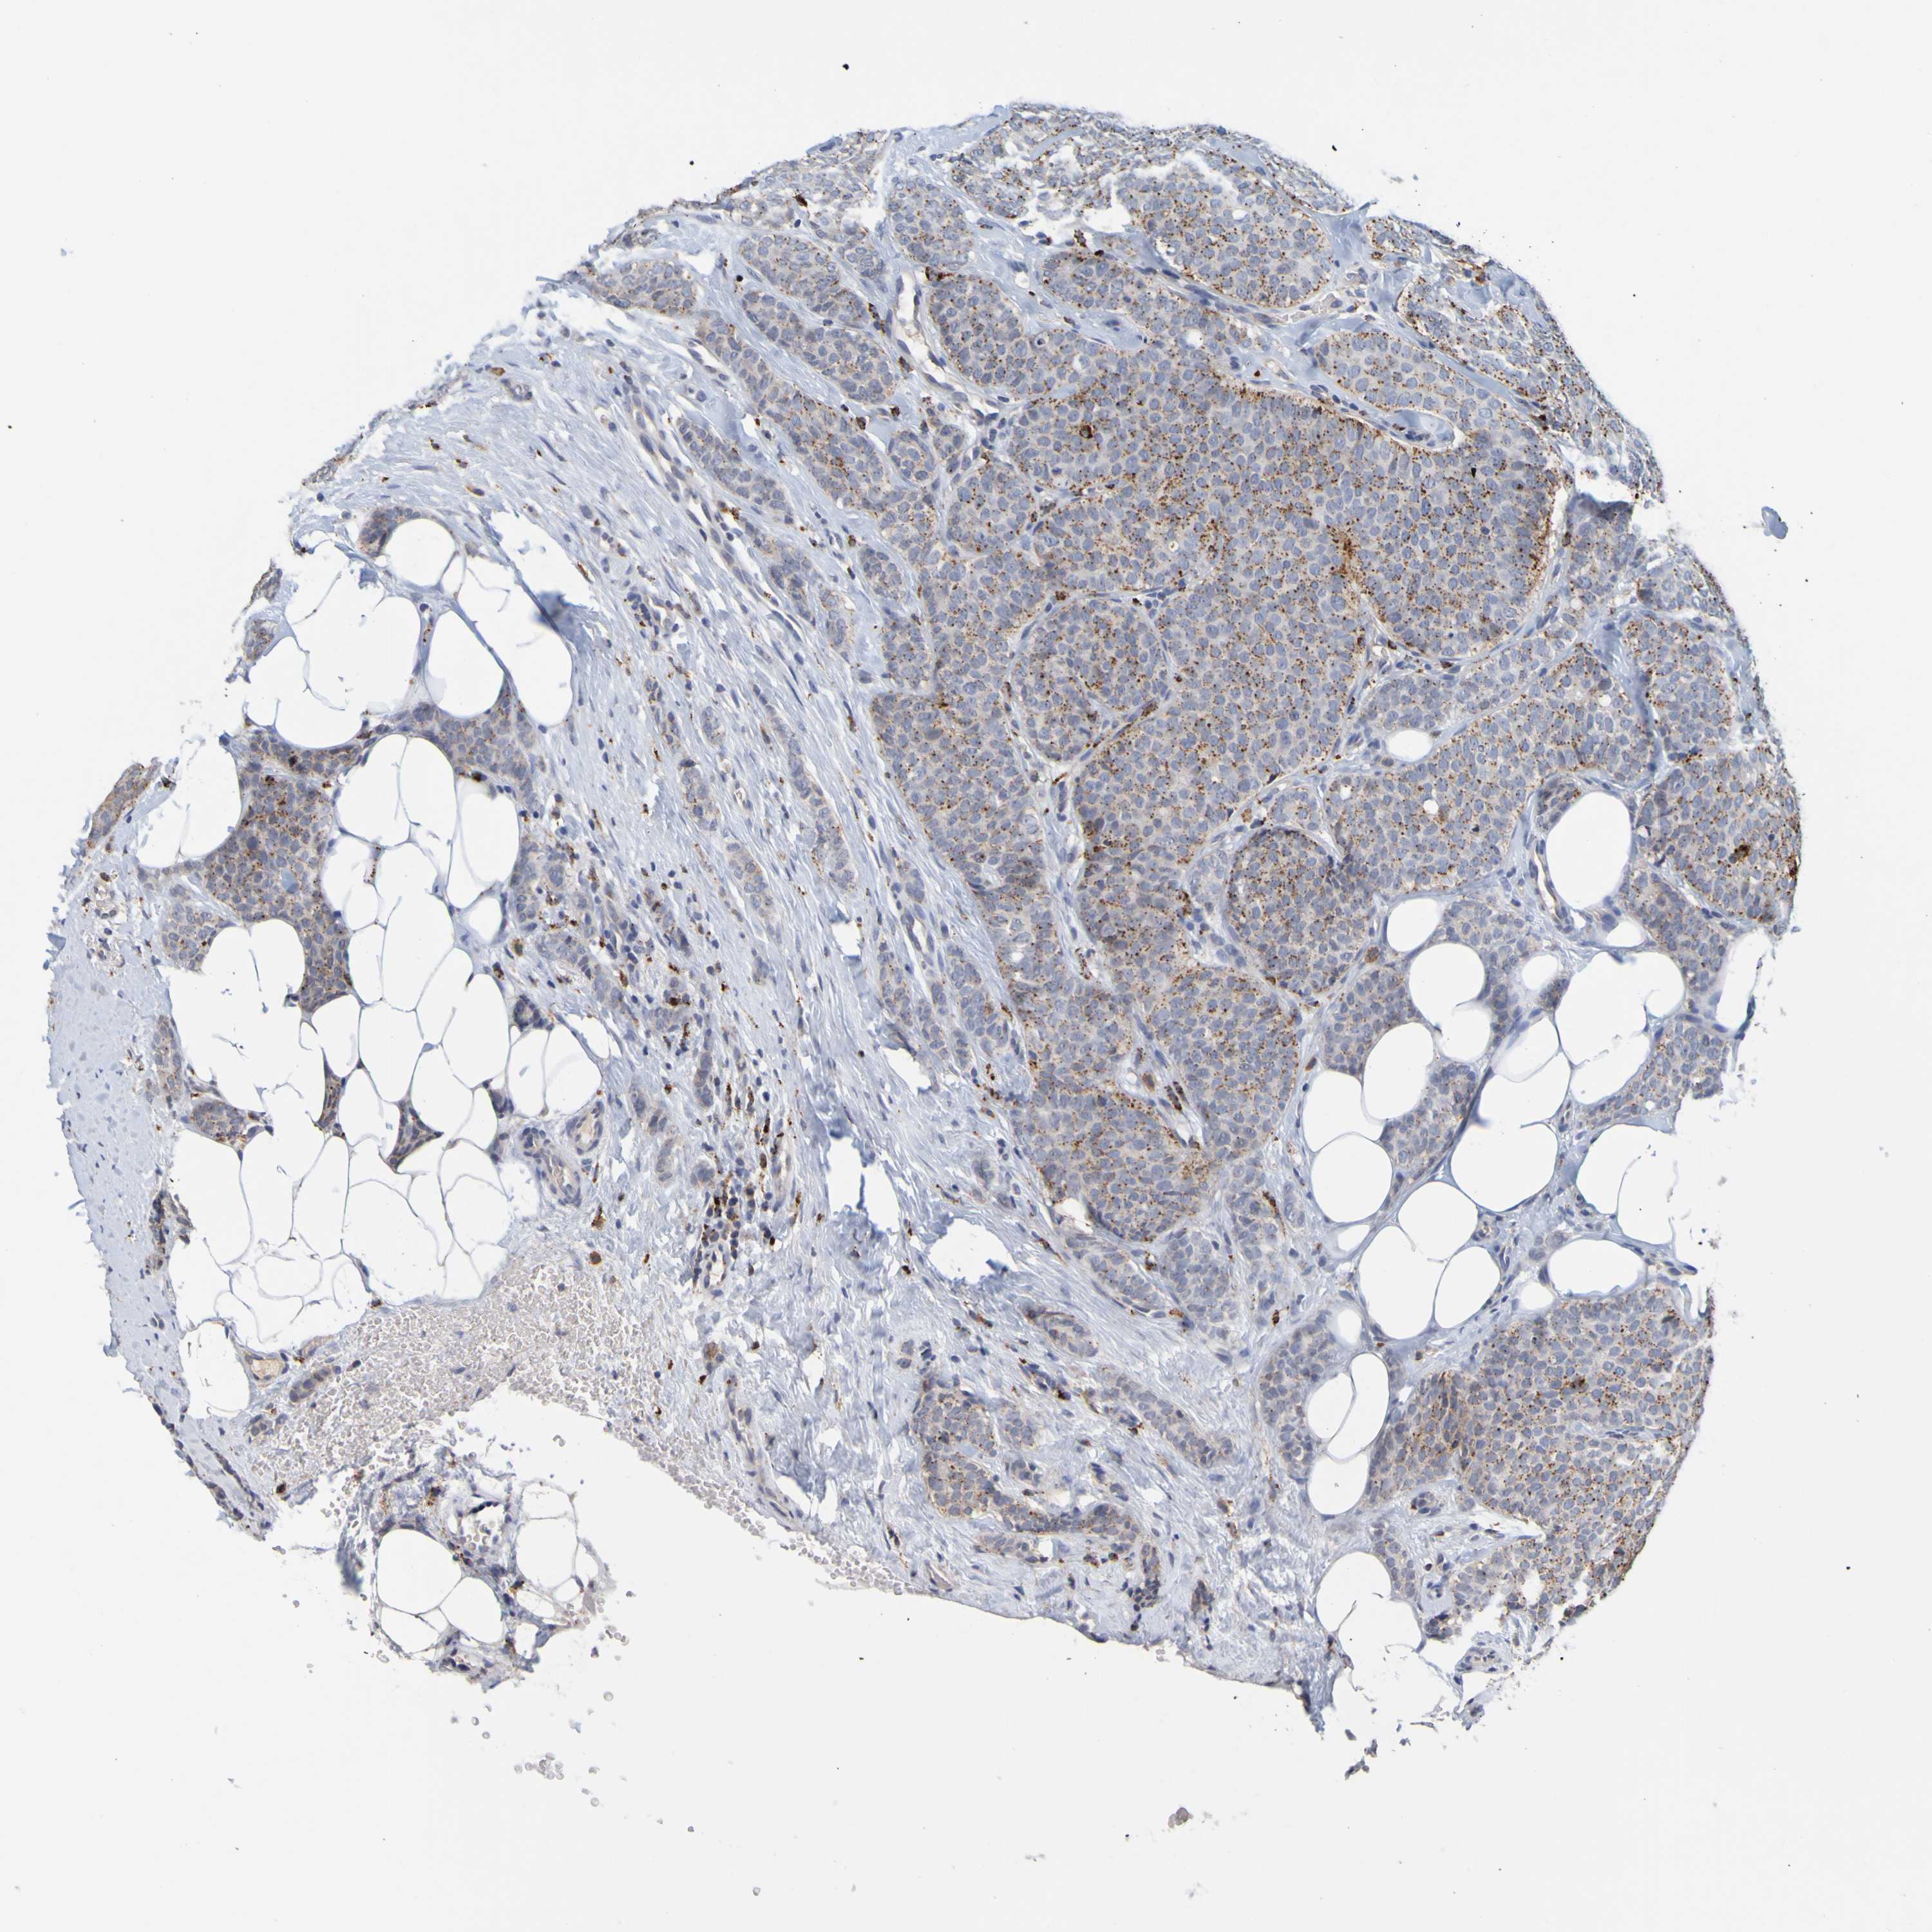

CANCER BREAST CANCER Show tissue menu

BRCA TCGA BRCA VALIDATION PROTEIN EXPRESSION